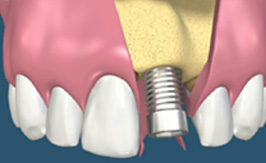

[발치 즉시 식립]

발치 즉시 임플란트

치료기간 단축을 위한 임플란트 시술

발치당일 임플란트를 식립하고 고정성 임시 보철물을 당일 시술하는 방법으로 치아가 완성되기 전까지 상당기간 기다려야 하는 불편함을 없앨 수 있는 시술법